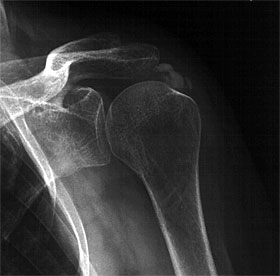

Es finden sich im Röntgen darstellbare Verkalkungen unterschiedlich

großen Ausmaßes und unterschiedlicher Lokalisation.

Die Abbildung zeigt ein Kalkdepot im Sehnenbereich

des M. Supraspinatus.